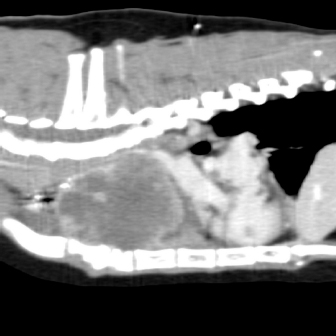

Fig. 2. Computerized tomography of the cranial mediastinal mass (coronal plane).

On physical examination, the cat had an unkept coat, reduced respiratory sounds cranially, and persistent stridor, but was otherwise bright and ambulatory. Computed tomography (CT) was performed using a Phillips Brilliance six slice CT. Multiphase contrast-enhanced CT images of the head, thorax, and abdomen were acquired with the cat in sternal recumbency (Figs. 1 and 2). A cranial mediastinal mass measuring 60 × 40 mm causing dorsal tracheal displacement toward the right was identified. With contrast administration, there was moderate enhancement of the periphery (+60 Hu) and poor central enhancement (+10 Hu). There was moderate to marked compression of the cranial vena cava, with a focal intraluminal contrast-filling defect at the cranial aspect of the vena cava just caudal to the mass. Here, the path of the cranial vena cava could not be completely traced, suggesting almost complete compression or invasion. There was no evidence of subcutaneous edema of the head or cervical region. Moderate volume of pleural fluid was bilaterally present. Multifocal, slightly branching soft tissue conglomerates largely following the bronchi of the caudal lobes toward the apex was noted, most likely to be bronchial disease with bronchiolar consolidation. Pulmonary metastatic neoplasia was considered to be unlikely. Surgical resection in the form of debulking was recommended on the basis that the large cranial mediastinal mass was most likely the cause of the cat’s clinical signs, and that reduction of gross disease should improve survival time as well as being more responsive to adjunctive treatment with chemotherapy. The cat was then started on mirtazapine (1.875 mg orally every 48 hours) and prednisolone (5 mg orally every 24 hours).